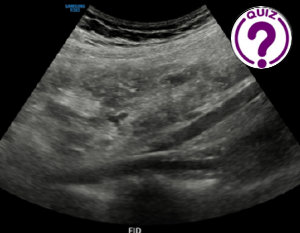

Case of the month June 2025: Diagnostics of an unknown process in the liver

1  Raphael Hauser; raphael.hauser@regionh.dk 2    Chenxi Huang; chenxi.huang.01@regionh.dk *  Correspondence: raphael.hauser@hotmail.com Clinical history A 50-year-old male with a medical history of congenital chloride diarrhea, intrahepatic biliary […]